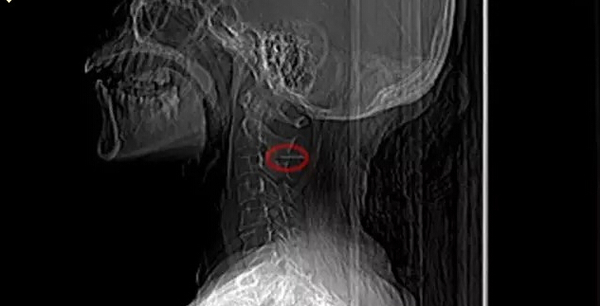

舌根部、咽喉部的检查需要医生用间接喉镜,观察舌根、会厌、以及梨状窝处是否有鱼刺。如发现有唾液滞留,应考虑鱼刺可能已进入食道。这时需进行食道吞钡餐透视检查,便可准确了解鱼刺在食道的位置,帮助治疗。